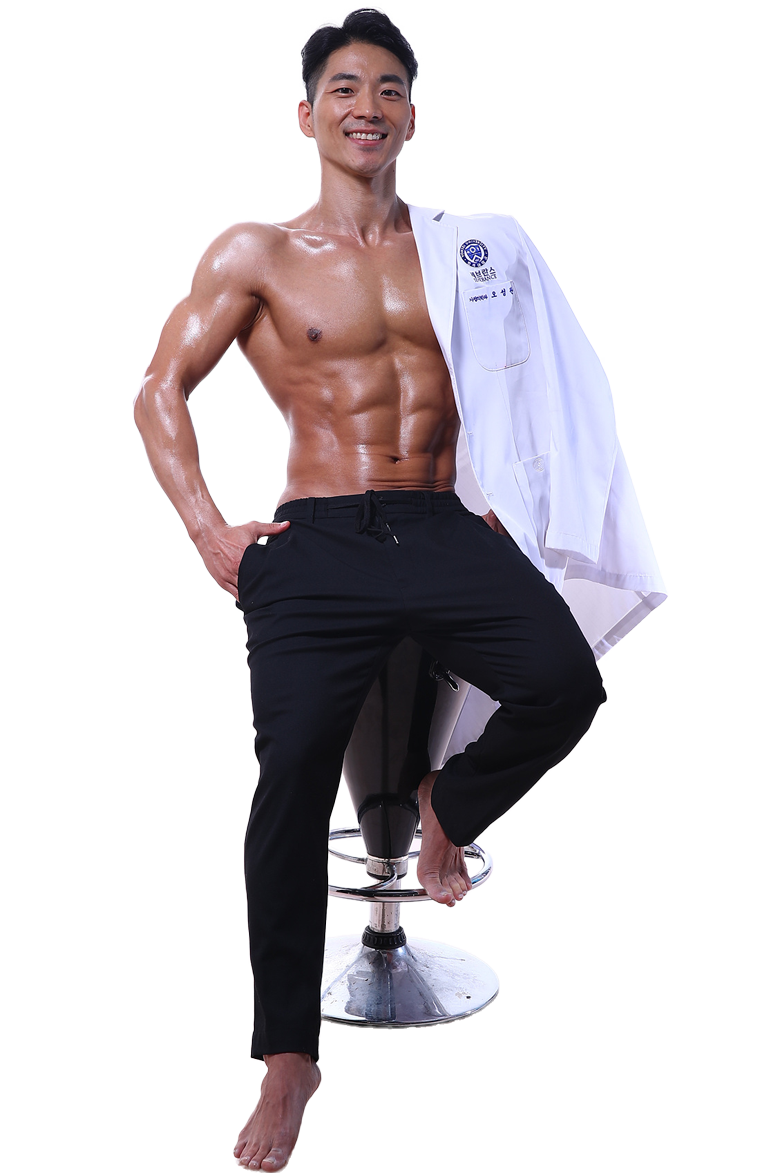

관절클리닉

관절클리닉

어깨통증, 무릎통증, 팔꿈치통증, 수부질환, 족부질환

비수술치료 클리닉

비수술치료 클리닉

도수/물리치료, 운동치료, 수액클리닉

척추클리닉

척추클리닉

목통증, 허리통증

비만통증클리닉

비만통증클리닉

체형 진단 및 운동치료

족부클리닉

족부클리닉

맞춤형 발진단 및 깔창제작